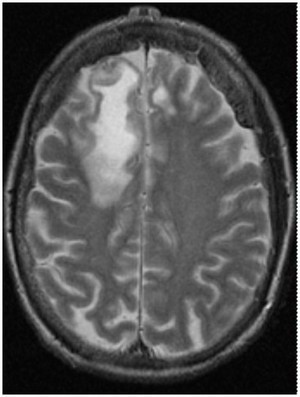

A 45 year old man with a 20-year diagnosis of HIV is brought to the physician by his partner after he notices cognitive changes in his partner. On neurological exam, the physician notes unilateral weakness. An MRI is ordered that reveals the following changes. What is the patient’s probably diagnosis given his presentation and underlying conditions?

Progressive multifocal leukoencephalopathy:

JC virus is a polyoma virus that causes a lytic infection of oligodendrocytes in immunocompromised persons.

70-80% of adults worldwide are seropositive for JC virus.

- Patients with compromised immune status especially AIDS patients are at risk for PML.